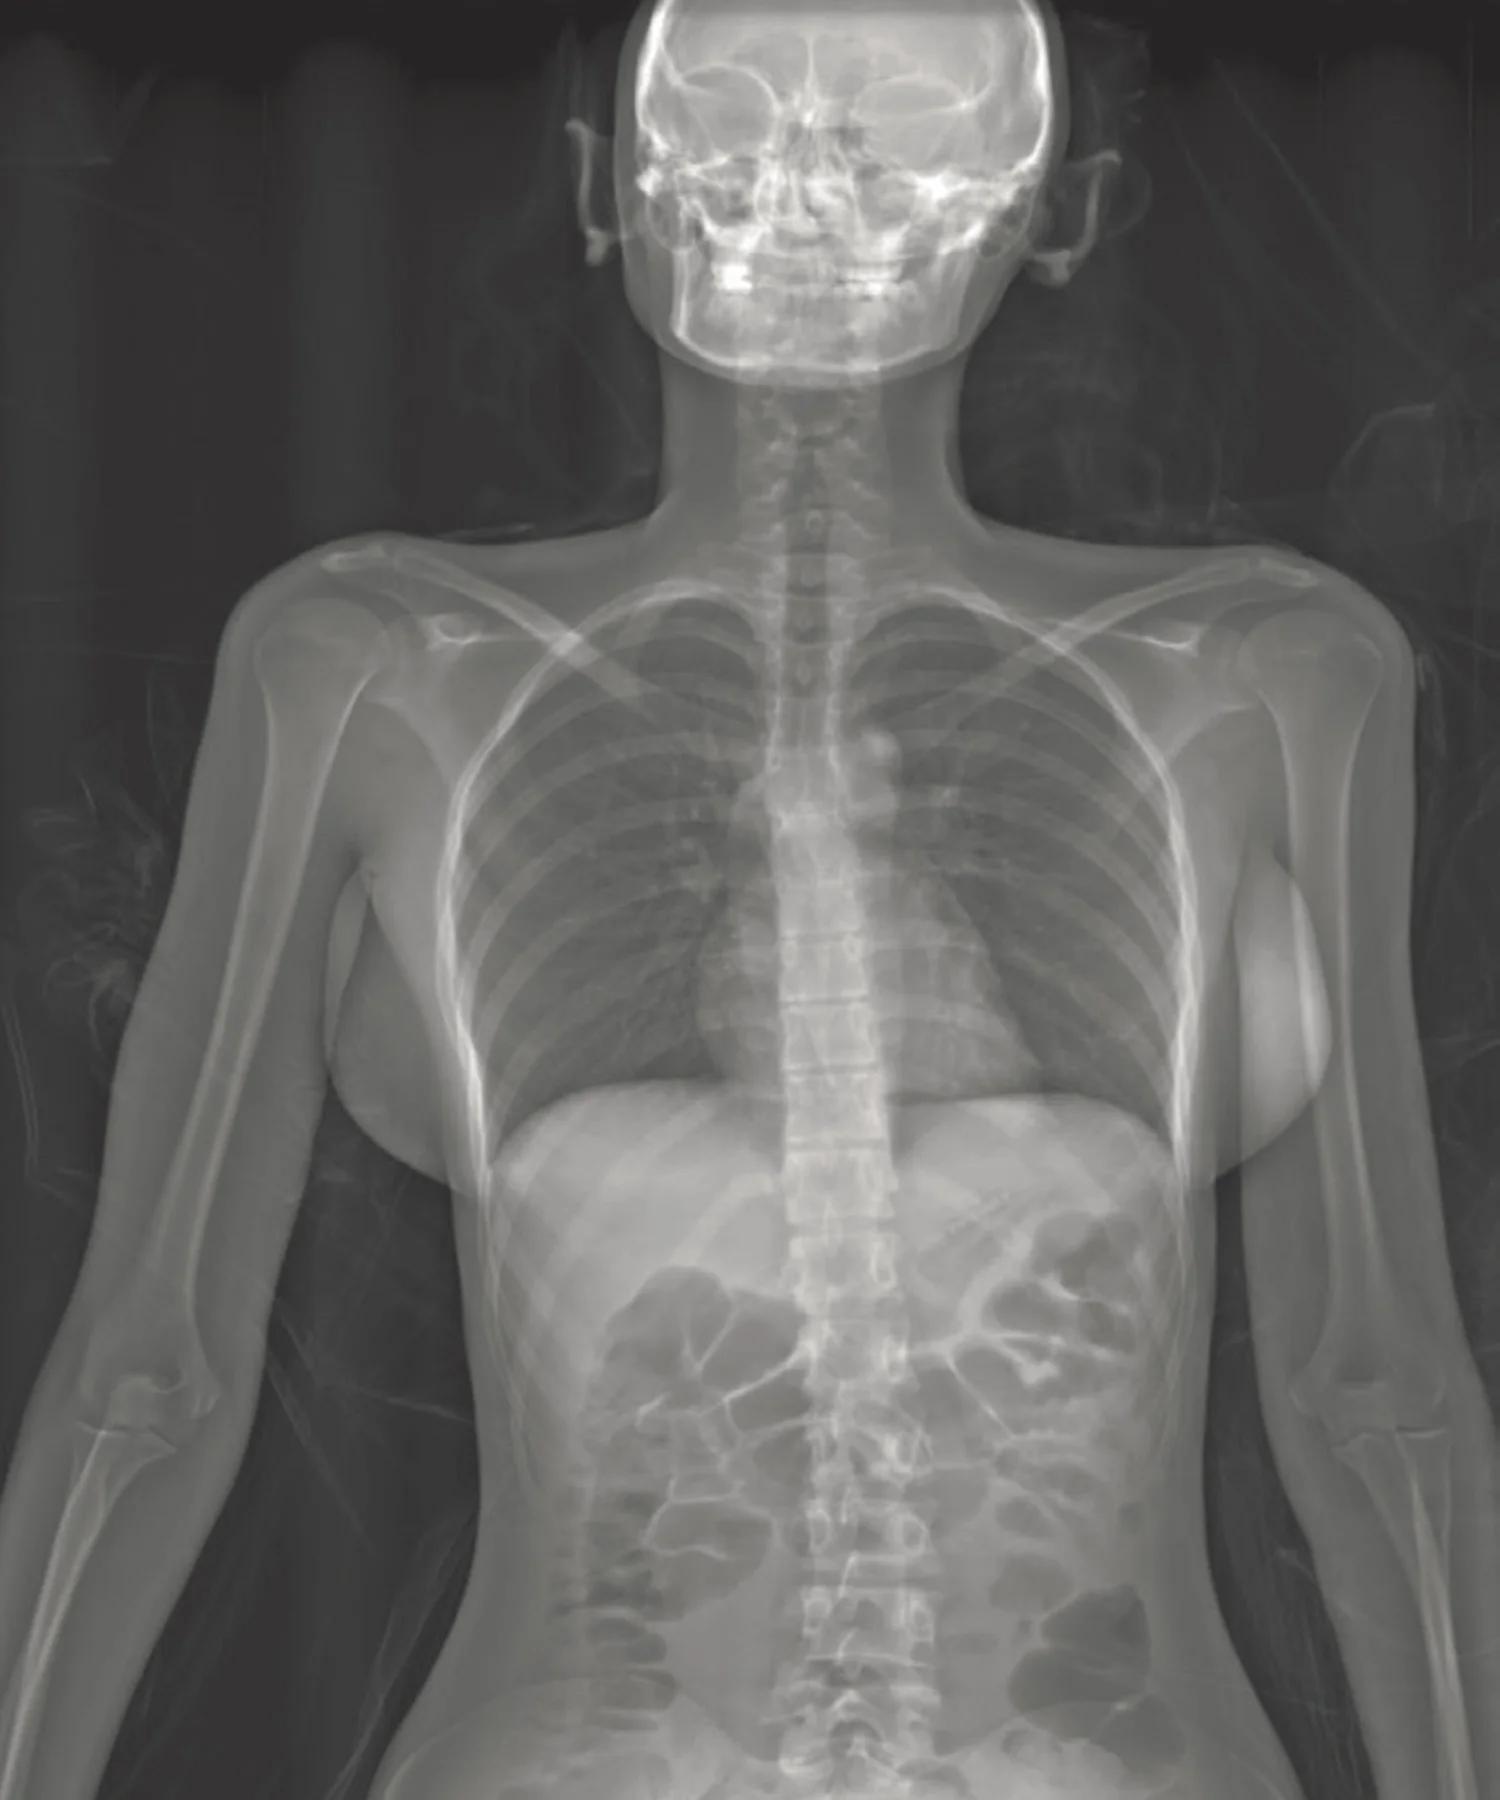

Рентгеновский эффект создает фантастические композиции в этих фотографиях девушки, чье тело становится прозрачным, демонстрируя скелет и внутренние органы. Она позирует в разных позах, ее силуэт светится загадочным свечением. Каждый кадр передает атмосферу научной фантастики и медицинского искусства. Ее кожа кажется полупрозрачной, позволяя увидеть кости и мышцы. Фотографии рассказывают о хрупкости человеческого тела и его внутренней красоте. Девушка то стоит в задумчивости, то делает грациозное движение. Эти иллюстрации вдохновляют на размышления о человеческой анатомии и уязвимости. Каждая картинка - это момент прозрения, когда внешнее уступает место внутреннему. Девушка воплощает образ современной Медузы, сочетающей красоту и загадочность.

Сквозь материю: тайны анатомии